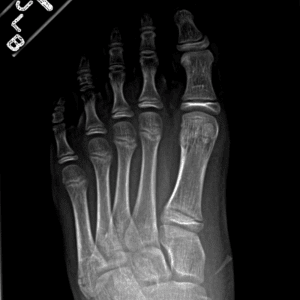

Pediatric Radiographs